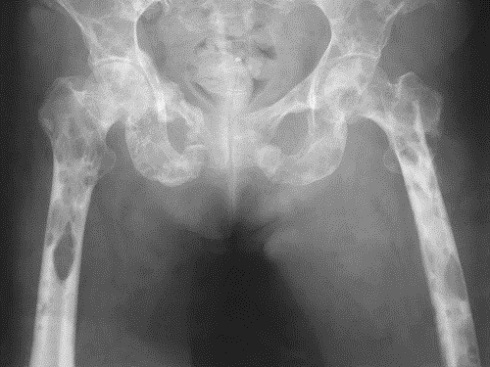

Визуальные материалы, связанные с болезнью Горхема-Стаута

Раздел: Альбом открытий